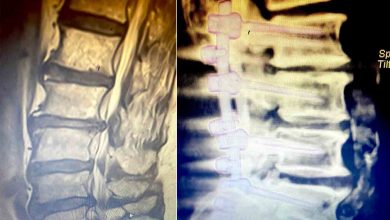

Omurgada yer alan boşlukların daralması ile meydana gelen ve yaşam kalitesini olumsuz etkileyen belde kanal darlığı (Lomber spinal stenoz) hastalığında…

Bel ve bacak ağrıları yaşayan ve kısmi felç nedeniyle yürüme zorluğu bulunan 34 yaşındaki Burcu Sönmez, Özel Sağlık Hastanesi’nde gerçekleştirilen…